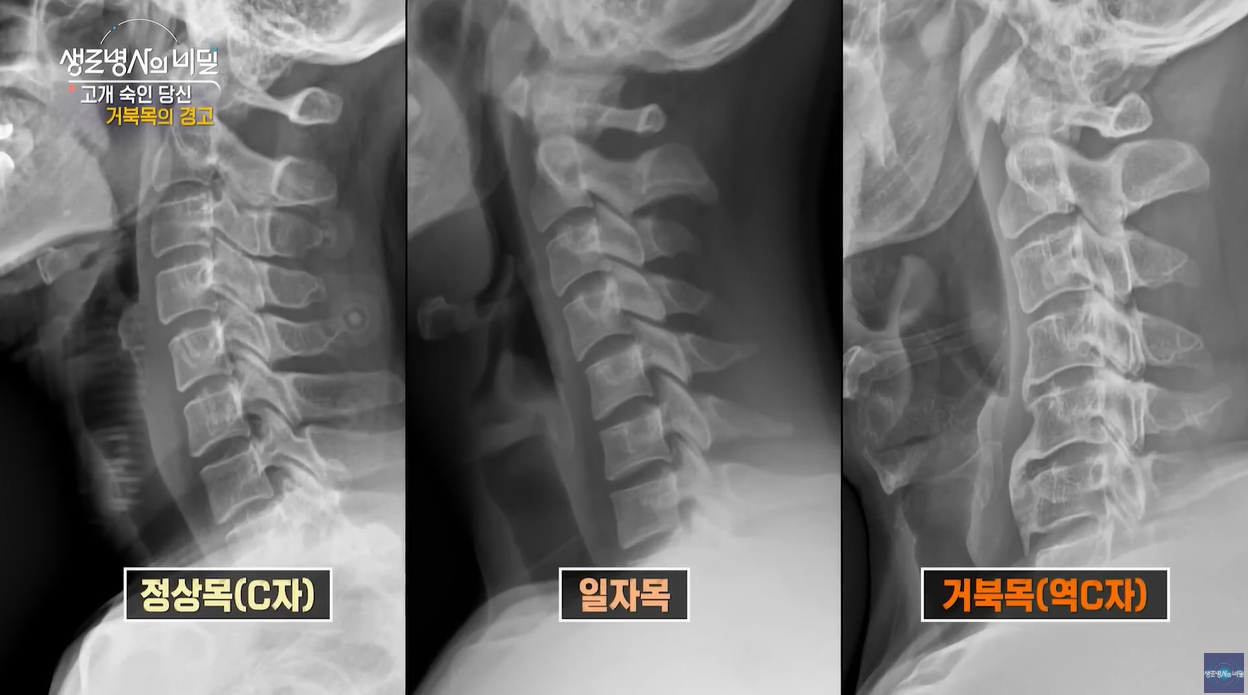

‘거북목’이라는 용어는 목뼈가 건강한 C자 곡선을 잃고 앞으로 쭉 뻗어나온 모습이 거북이의 목과 비슷하다고 해서 붙은 이름입니다.

목뼈는 보통 완만한 C자 곡선을 그리며 머리의 무게를 자연스럽게 분산시키는데요,

하지만 스마트폰, 컴퓨터, 태블릿 등 화면을 보느라 목을 앞으로 내미는 시간이 길어지면서 이 곡선이 펴지거나 반대로 일자로 변형되는 문제가 발생합니다.

● 정상 목뼈: C자 형태 → 무게 분산과 충격 완화

● 거북목: 일자 혹은 앞쪽으로 뻗음 → 근육 과사용, 관절 압박 증가